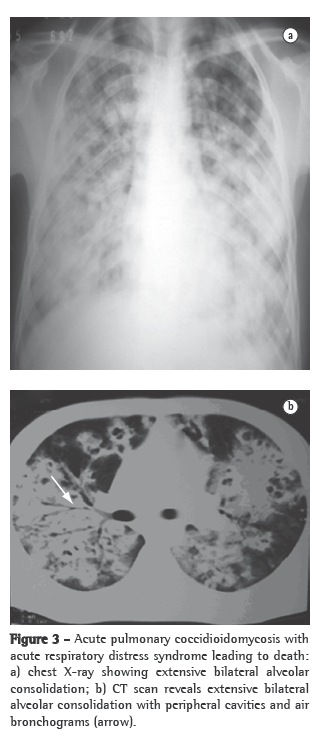

Nonspecific tests that are useful for the evaluation of patients include X-rays and CT scans of the affected site, principally of the chest, and can greatly aid in the diagnosis (Figures 2 and 3). The most common findings on chest X-rays are multiple lung nodules of peripheral distribution, associated with parenchymal consolidation. CT scans of the chest reveal peripheral lung nodules that are predominantly cavitated.(29,39)

The most common form of presentation of coccidioidomycosis, primary pulmonary coccidioidomycosis is characterized by pulmonary manifestations that generally appear one to three weeks after exposure to the fungus. Approximately 60% of the infected individuals evolve to spontaneous cure without clinical or radiological manifestations. The remaining 40% generally present symptoms of acute respiratory disease, mimicking the flu, accompanied by fever, night sweats and cough or pleuritic chest pain, or a combination of the two. The manifestations appear between 10 and 15 days after exposure to the fungus, and the intensity of the symptoms depends directly on the infective load, ranging from the flu to a severe, nonspecific respiratory infection, accompanied by high fever, chest pain and cough with or without expectoration, as well as by general symptoms or allergic manifestations, particularly erythema nodosum. Primary pulmonary coccidioidomycosis generally resolves spontaneously within 30-60 days, even without antifungal treatment. However, approximately 5% of these patients develop residual pulmonary lesions (generally solitary nodules) that are asymptomatic in most patients. These cases are often diagnosed after surgical removal due to suspected lung cancer. Another 5% of these patients develop thin-walled cavities, solitary and juxtapleural, that might resolve spontaneously in approximately 2 years. In certain cases, principally in diabetic or immunocompromised patients, the acute pulmonary form does not resolve; it progresses to chronic pneumonia and is characterized by the formation of pulmonary cavitation. The lungs might also be diffusely affected as a result of the inhalation of a large quantity of infective arthroconidia or as a late and secondary presentation resulting from hematogenous dissemination. These forms present with multiple diffuse infiltrates, the largest of which might present cavitation accompanied by severe respiratory manifestations, which can lead to respiratory failure and are more commonly observed in immunocompromised patients. The disease might progress to death, mimicking septic shock, accompanied by acute respiratory distress syndrome, with high mortality rates.(13,27)